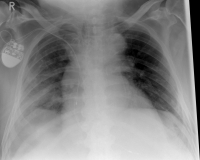

As a rule, the rib fracture is diagnosed by X-ray. In severe cases or ambiguous X-ray findings, a layer imaging, for example computer tomography (CT), can also be performed.

Pneumothorax / tension pneumothorax

In some cases, the sharp rib fragments cause lung or outer chest wall injuries. As a result, air can enter the gap between the lung and chest wall and cause a so-called pneumothorax, which must be treated by drainage.

In rare cases, a so-called tension pneumothorax may develop, which under certain circumstances can also be life-threatening. Due to an injury-related valve mechanism, air from the lungs flows into the gap between the lungs and the chest wall, but can not escape. As a result, the organs are shifted in the chest and concentrated, so that the circulatory function is impaired. It requires, in these cases, an immediate delimbing in the hospital or by an emergency physician.

Hemothorax

If blood accumulates in the gap between the lungs and the chest wall due to the injury of a blood vessel or the lungs, this is called hematothorax. If there is still air in the gap, it is a hematopneumothorax. Both the hematopoietic and the hematopneumothorax must often be treated with a drainage.